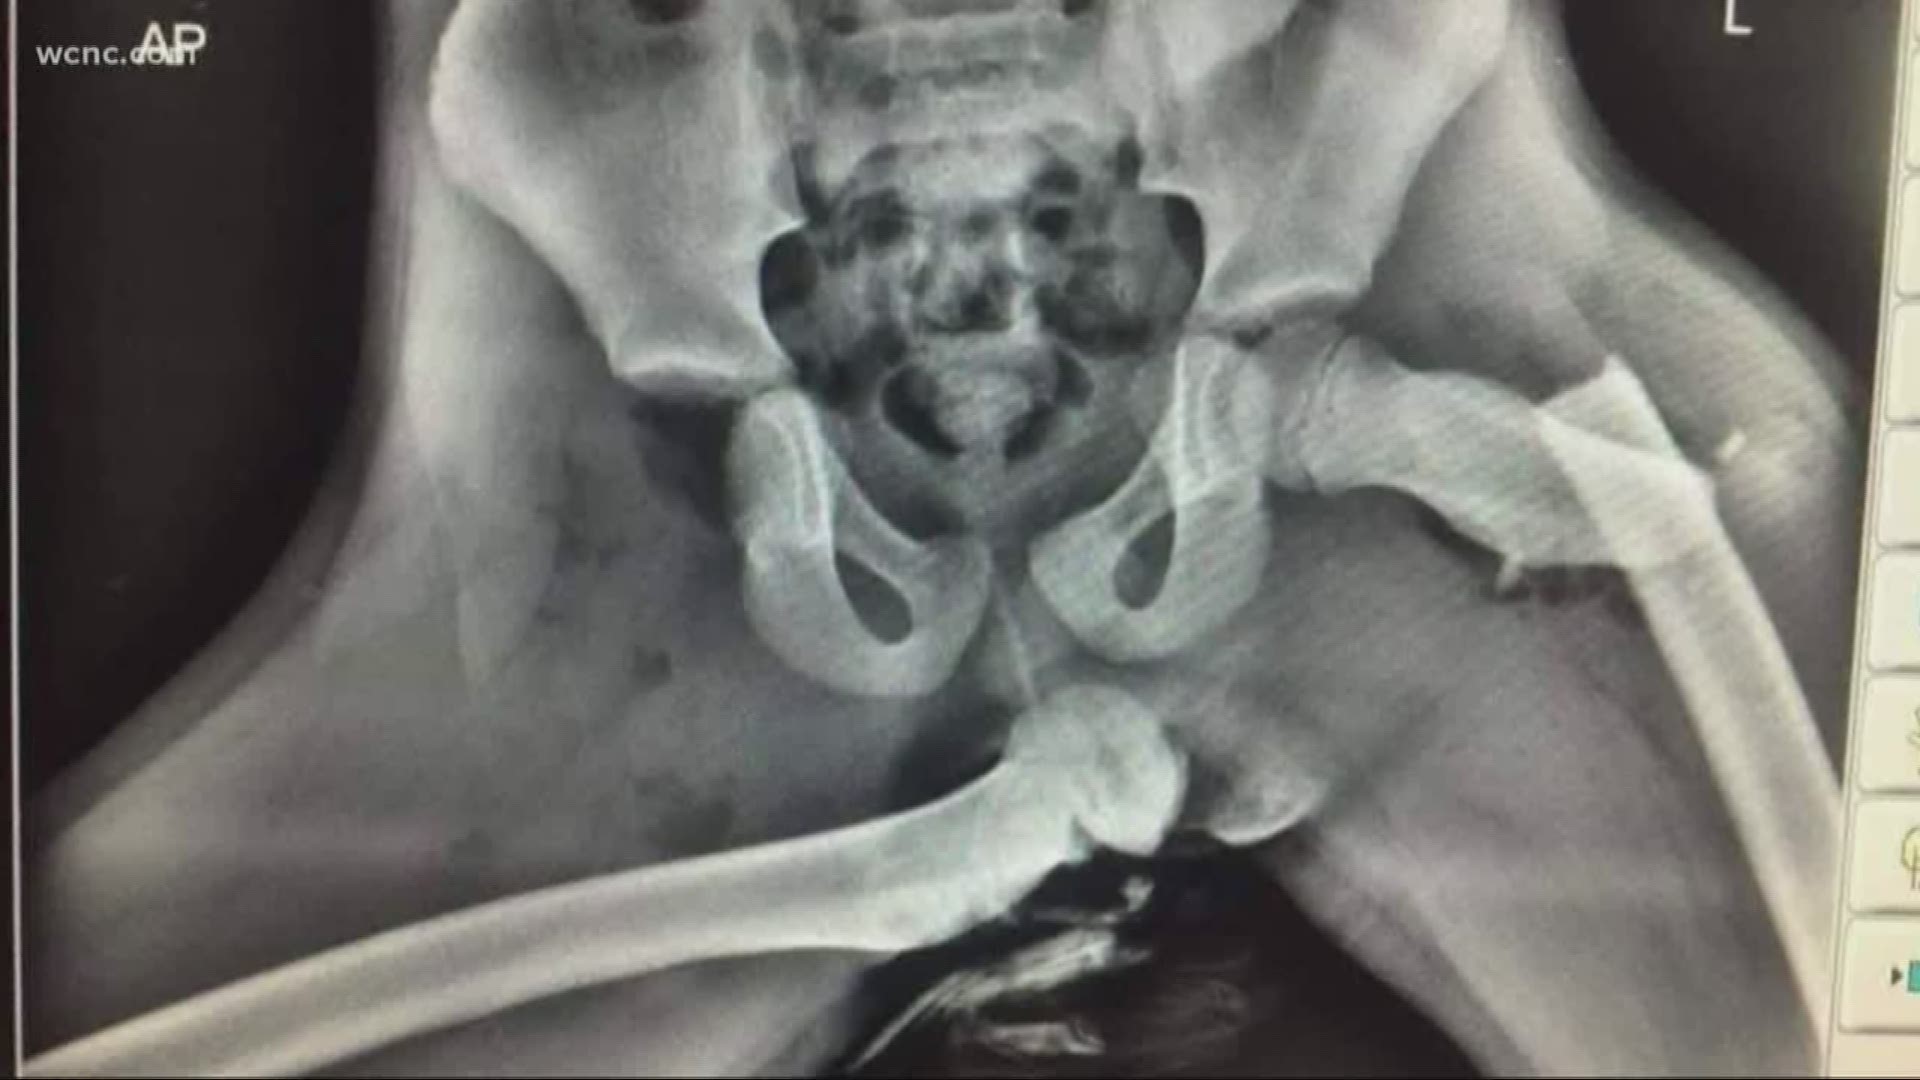

EMT. Get ur feet off the dash please.

I quit putting my feet on the dashboard after I saw that one X-ray picture. You know which one I'm talking about.

Load More Replies...Broken hips, legs, ribs, and more await you when your feet are on the dash.